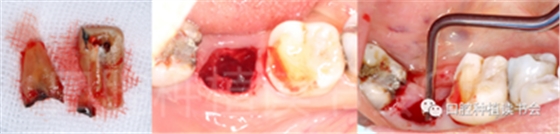

圖1 無(wú)法保留的上頜隱裂后牙,拔牙后即刻種植。

后牙區(qū)或者是非美學(xué)區(qū)即刻種植,對(duì)于患者和臨床醫(yī)生而言,存在一些明顯的優(yōu)勢(shì);比如更小的外科創(chuàng)傷、更短的愈合周期、更少的椅旁時(shí)間、更高的患者接受度以及更低的治療費(fèi)用等。除此之外,在上頜后牙區(qū)即刻種植還可以減少上頜竇的氣化現(xiàn)象【Sharan等.2008】;但并非所有的后牙位點(diǎn)都適合即刻種植,后牙區(qū)即刻種植對(duì)醫(yī)生的技術(shù)和經(jīng)驗(yàn)要求更高;由于解剖等諸多條件的差異,美學(xué)區(qū)即刻種植的臨床注意事項(xiàng)與后牙區(qū)即刻種植存在諸多不同之處;與本文旨在通過(guò)詳細(xì)的文獻(xiàn)回顧及臨床案例對(duì)后牙區(qū)即刻種植治療提供臨床參考。